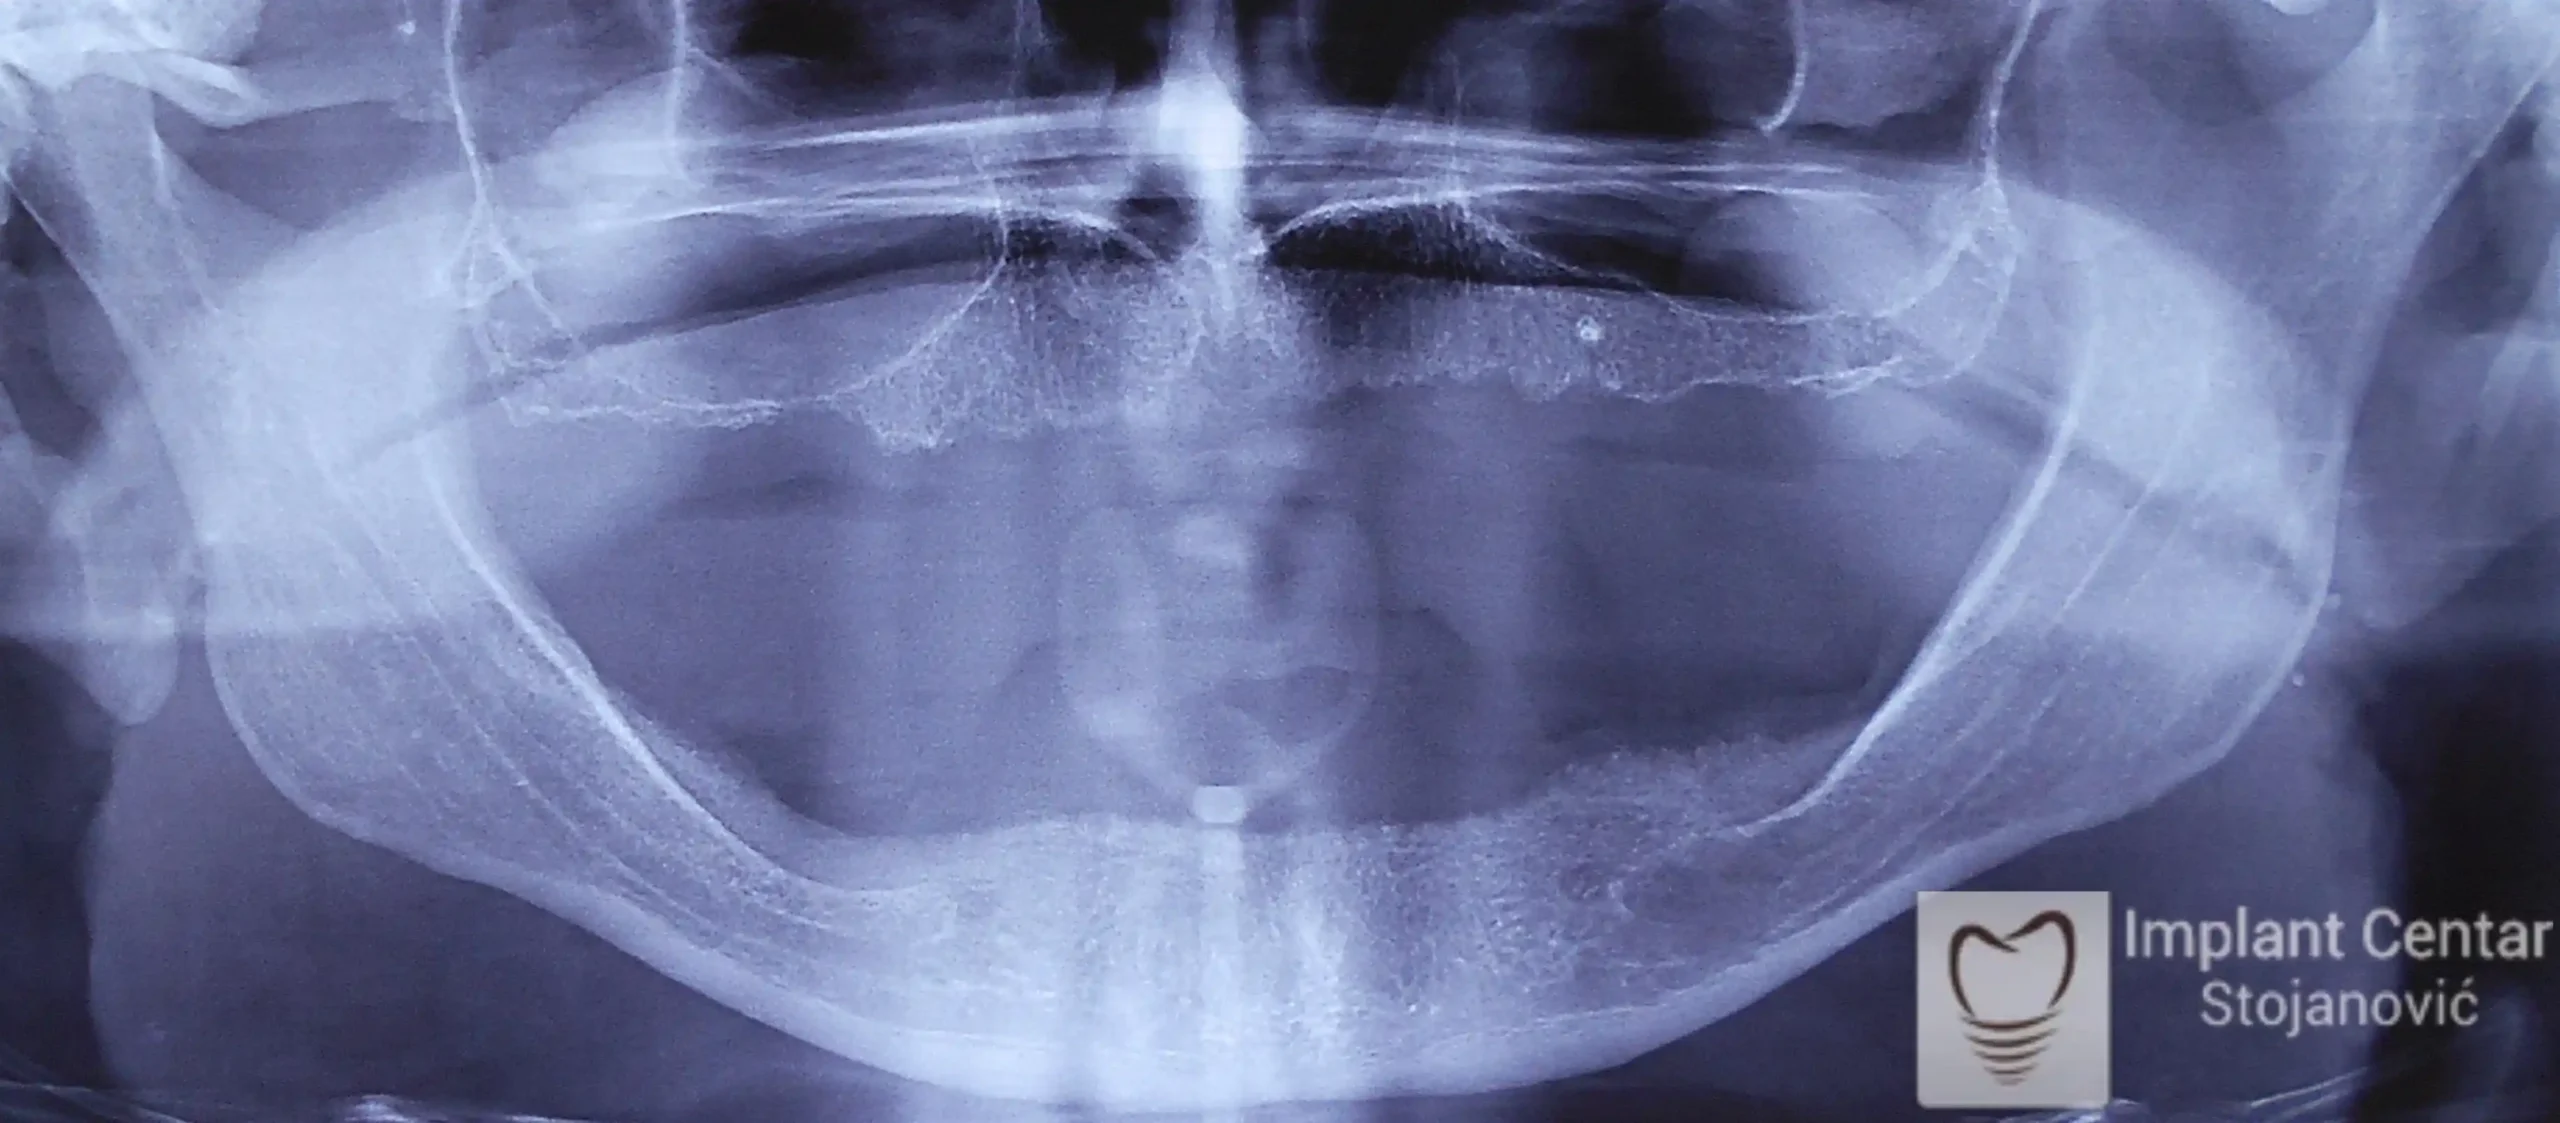

Pacijent iz USA sa ratnom traumom zadobijenom tokom rata u BiH Dum-Dum metkom.

Pacijentu su predlagana razna resenja i kod nas i u inostranstvu, koja pacijent nije zeleo da prihvati jer nije zeleo vise da nosi protezu.

PRISTUPILI SMO RESAVANJU DEFEKTA GORNJE VILICE SA CILJEM MAKSIMALNOG KOMFORA I SIGURNOSTI ZA PACIJENTA UGRADNJOM IMPLANTATA I IZRADOM FIKSNOG METALOKERAMICKOG MOSTA